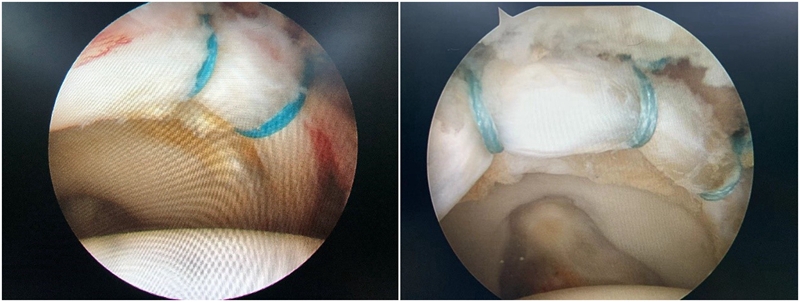

2.盂唇损伤的治疗:盂唇损伤广泛存在于髋关节撞击综合征中。对于存在修复条件的盂唇损伤,目前推荐行盂唇修复术;而对于盂唇严重磨损无法修复或横断的情况,则可考虑行盂唇清理、盂唇部分修复或盂唇重建术。手术原则是对损伤的髋臼盂唇尽量予以缝合修复,恢复髋臼盂唇的解剖结构,从而恢复髋臼盂唇的功能,避免由于髋臼盂唇缺损造成的髋关节退变。

图10 髋关节盂唇损伤及修复